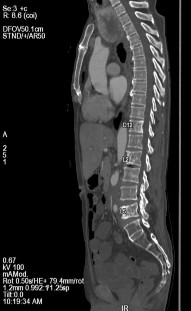

Bệnh nhân được chụp cắt lớp vi tính toàn thân, kết quả:

- Tuyến tiền liệt không to, không thấy tổn thương xâm lấn ra phía

ngoài.

- Nhiều tổn thương di căn lan toả nhu mô 2 phổi kèm theo lớp dịch

mỏng màng phổi 2 bên.

- Di căn hạch trung thất, hạch sau phúc mạc.

- Nhiều ổ đặc xương thứ phát ở xương sườn 4 phải, xương sườn 8 trái và nhiều đốt sống (thấy rõ ở D12, L2, L5).

Hình C. Hình ảnh chụp CT tại thời điểm kháng cắt tinh hoàn

Bệnh nhân được chẩn đoán Ung thư tuyến tiền liệt kháng cắt tinh hoàn, điều trị Dipherelin và Docetaxel/Prenisolone.